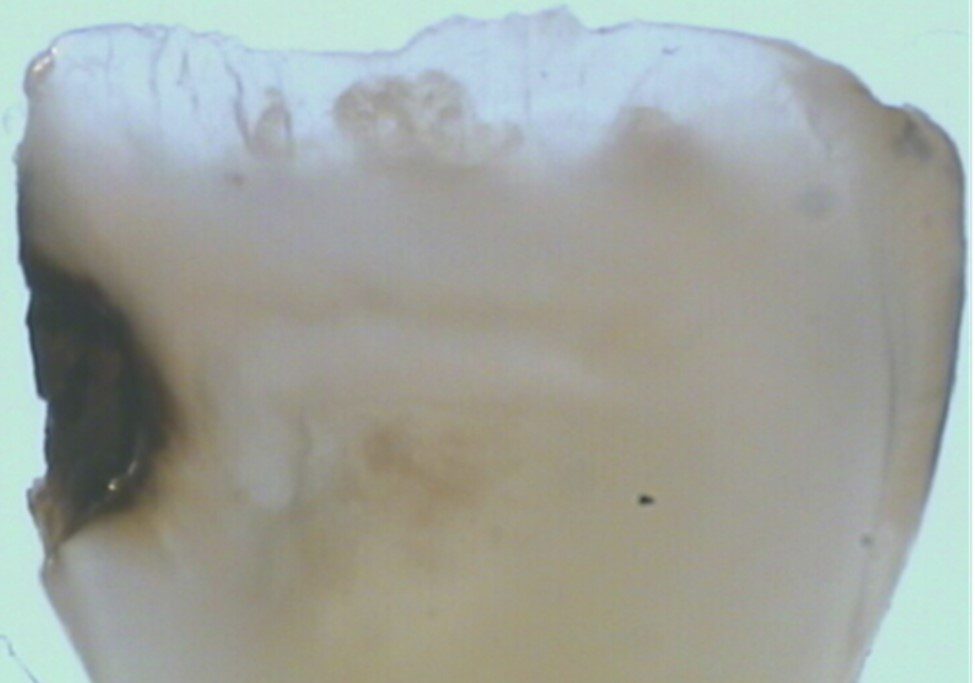

Thứ hai, Fluoride thúc đẩy quá trình tái khoáng hóa tổn thương sâu răng. Fluoride đã được chứng minh là phản ứng với Hydroxyapatite và tạo ra Canxi Fluoride, một nguồn chứa Fluoride và tạo điều kiện cho quá trình tái khoáng hóa sau đó. Một số nghiên cứu đã báo cáo độ cứng vi mô của lớp bề mặt xoang sâu sau khi sử dụng SDF có thể so sánh với ngà răng lành. Trên bề mặt sâu răng bị chặn lại sau khi điều trị bằng SDF, người ta quan sát thấy có vùng tái khoáng cao.

Nhược điểm cố hữu của SDF là các tổn thương sâu răng sẽ bị ố đen sau khi bôi. SDF ngăn chặn sự tiến triển của sâu răng bằng cách hình thành một lớp cứng, đen, không thấm nước trên bề mặt răng và có khả năng chống sâu răng.